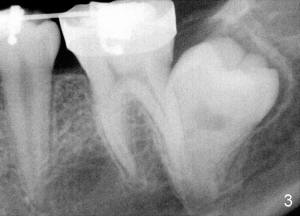

Impacted Lower 2nd Molar

Xin Wei, DDS, PhD, MS 1st edition 09/07/2011, last revision 09/07/2011